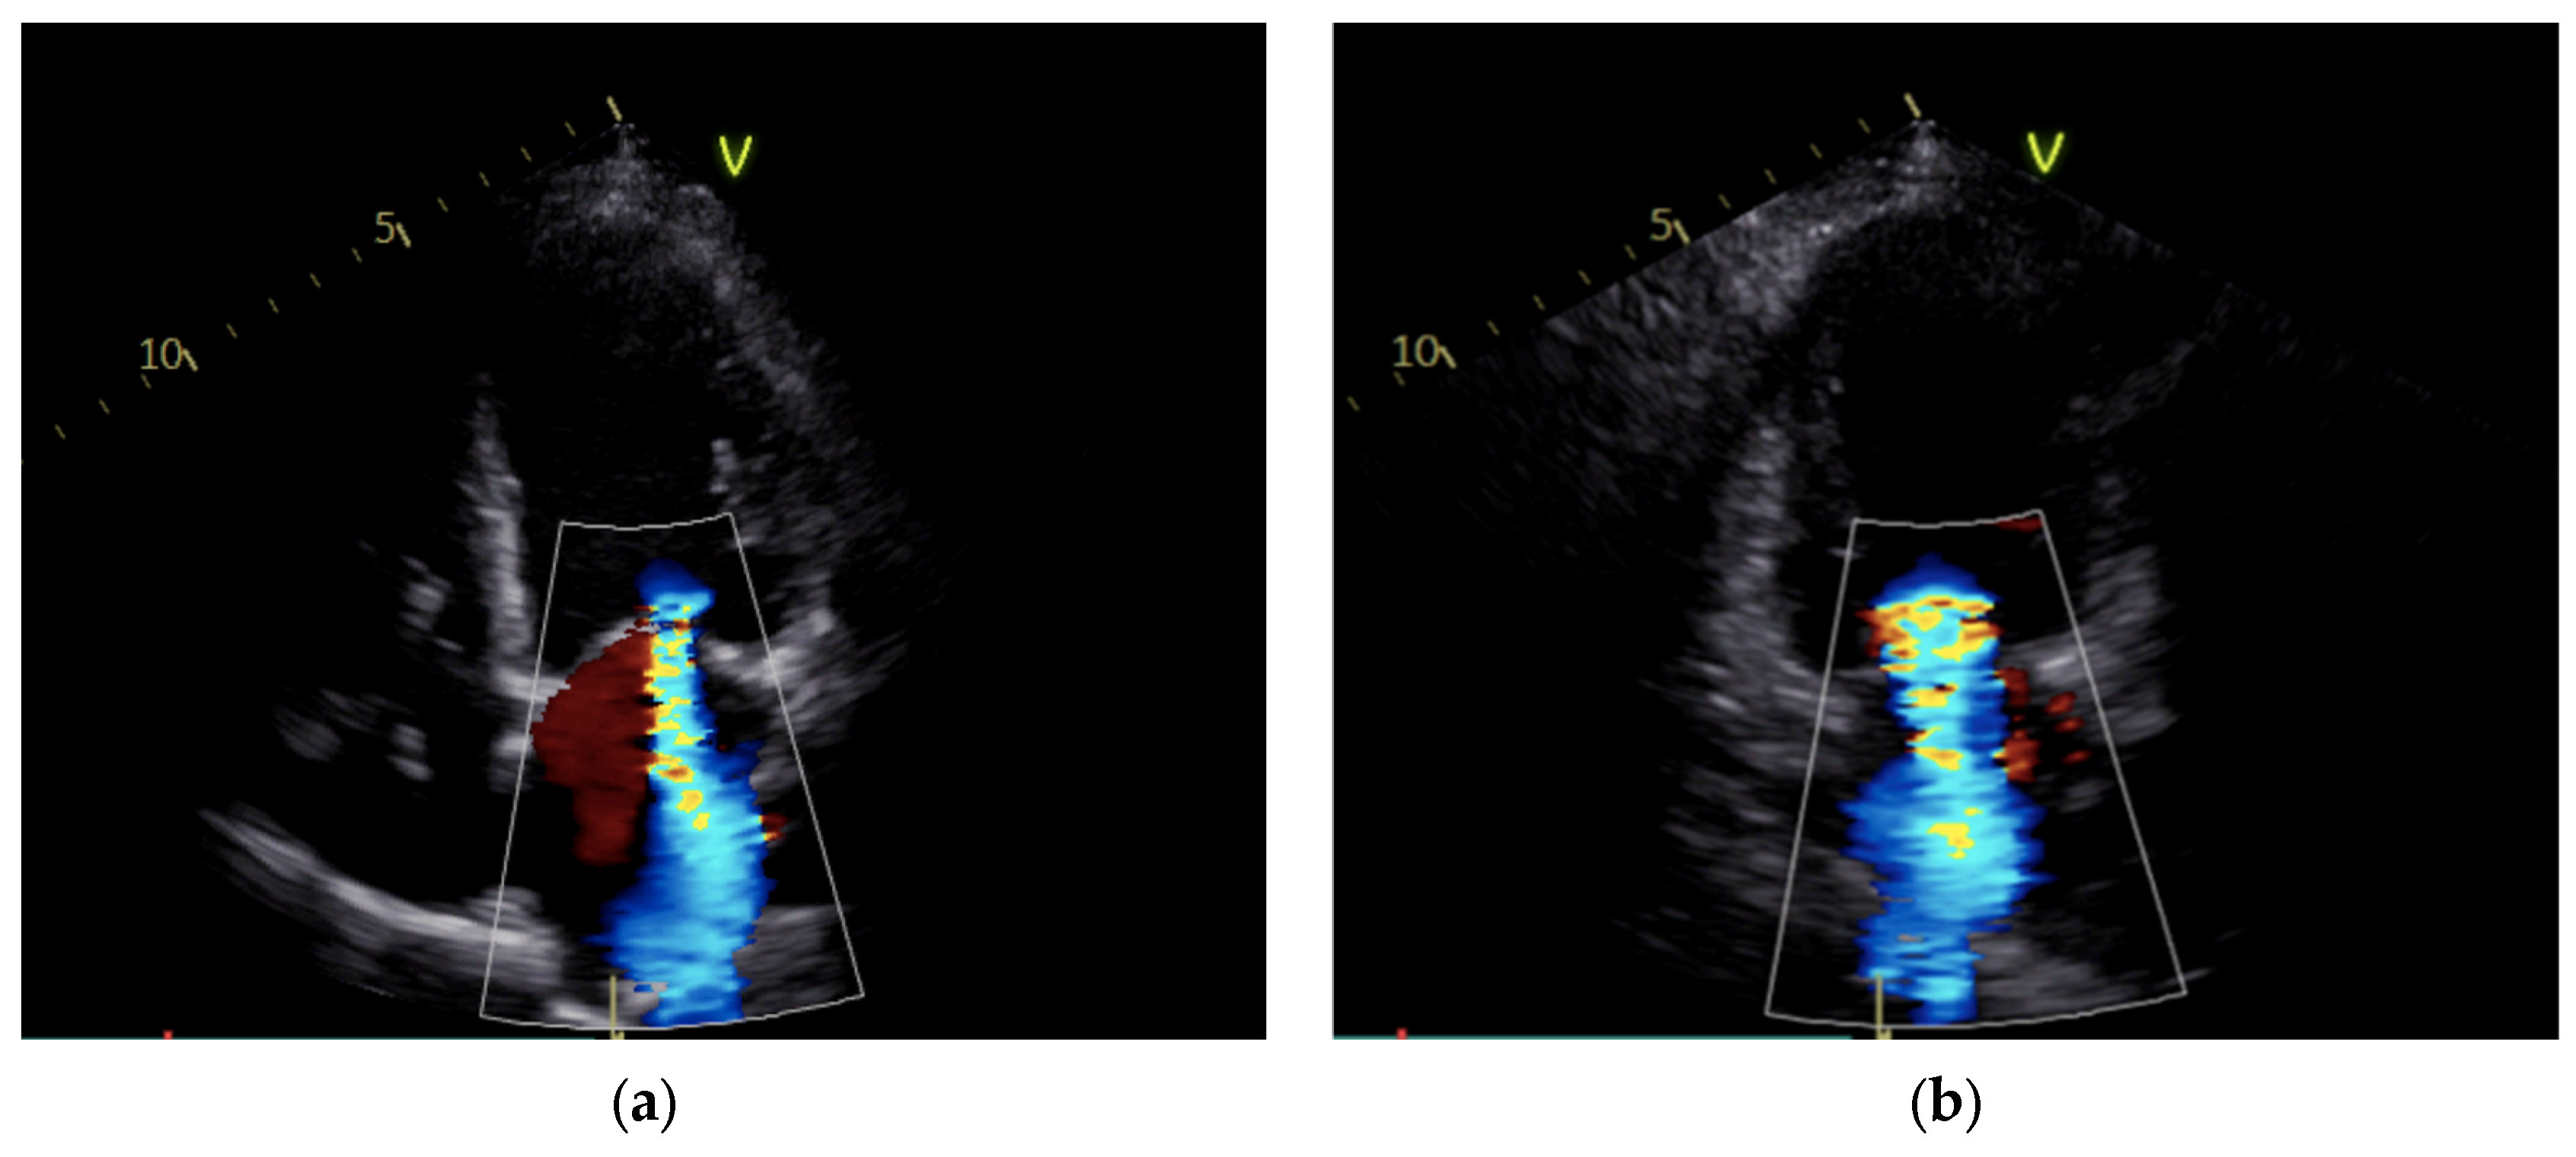

Upon improvement of the hemodynamic condition, the IABP was surgically removed, and the patient’s low-dose inotropic support was continued. After IABP removal, the patient encountered rapid clinical deterioration and the emergence of low cardiac output (Table 2). Indeed, the hemodynamic parameters demonstrated a sudden notable elevation in pulmonary pressures and a decline in the cardiac index (CI) from 1.8 to 1.1 L/min/m2 (Table 2). Echocardiography revealed massive MR due to a coaptation defect of the leaflets (Figure 1, Supplementary Materials Videos S1 and S2).

Figure 1.

Mitral regurgitation after IABP removal: severe regurgitation is visible in apical 4-chamber view (a) and apical 2-chamber view (b).